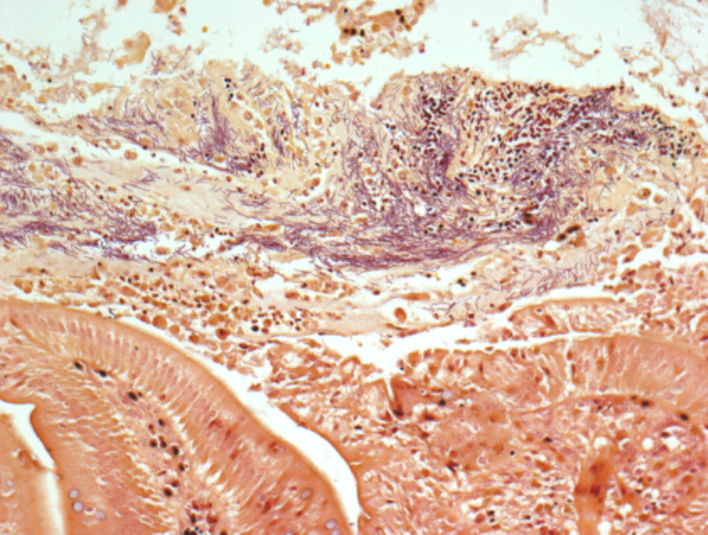

The AHL has recently validated an immunohistochemical (IHC) test for Listeria monocytogenes in formalin-fixed, paraffin-embedded tissue sections. This test is very helpful in cases with histologic lesions typical of listeriosis, but for which fresh tissue is not available for bacterial culture.

The beauty of IHC lies in the ability to co-localize staining for infectious antigens and histologic lesions, enhancing the value of test results (Figure 1).